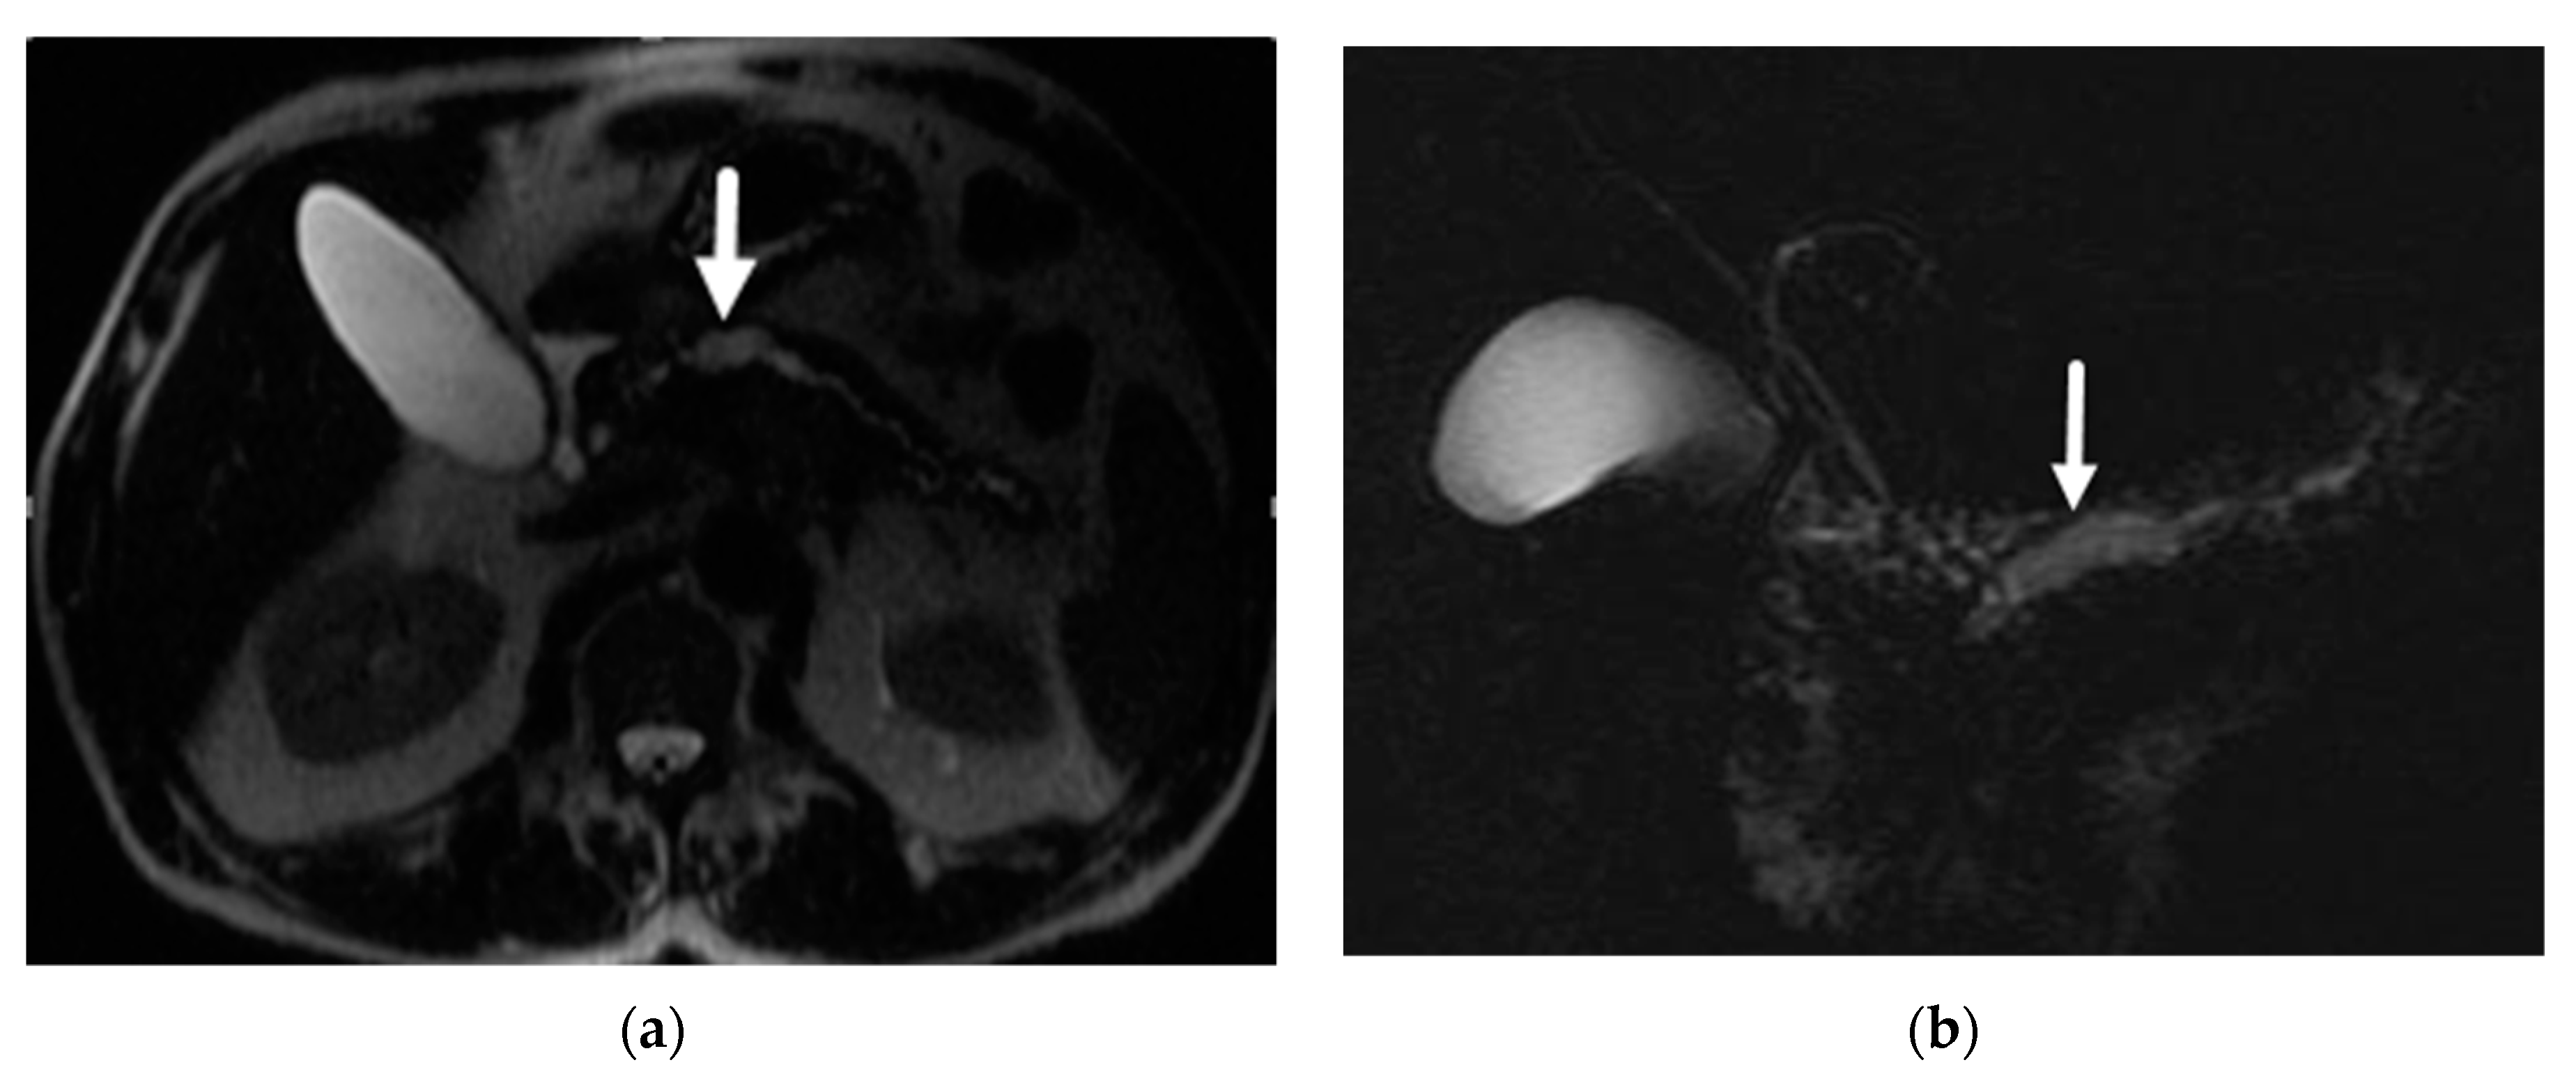

- Mamone, G.; Barresi, L.; Tropea, A.; Di Piazza, A.; Miraglia, R. MRI of mucinous pancreatic cystic lesions: A new updated morphological approach for the differential diagnosis. Updates Surg. 2020, 72, 617–637. [Google Scholar] [CrossRef] [PubMed]